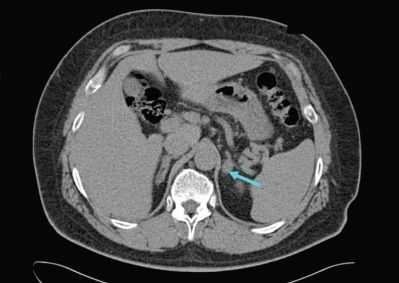

- Инструментальная визуализация. УЗИ надпочечников и радиоизотопное сканирование (сцинтиграфию) надпочечников используют для выявления имеющихся патологических изменений и уточнения их характера (гиперплазия, опухоль), КТ надпочечников и МРТ надпочечников - для определения локализации и величины альдостеромы.

Для выяснения природы поражения (альдостерома, диффузно-узелковая гиперплазия, рак) используют методы топической диагностики: УЗИ надпочечников, сцинтиграфию, КТ и МРТ надпочечников, селективную венографию с одновременным определением уровней альдостерона и кортизола в крови надпочечниковых вен. Также важно установить заболевание, вызвавшее развитие вторичного гиперальдостеронизма с помощью исследований состояния сердца, печени, почек и почечных артерий (ЭхоКГ, ЭКГ, УЗИ печени, УЗИ почек, УЗДГ и дуплексное сканирование почечных артерий, мультиспиральная КТ, МР-ангиография).